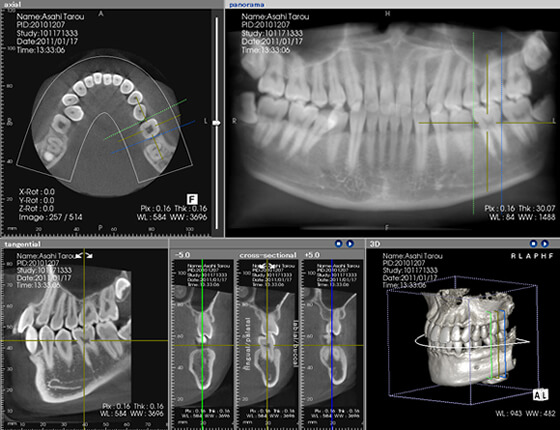

デジタルCT

画像"

歯や頭蓋骨の状態などを三次元の立体画像で撮影できるX線画像撮影装置です。デジタル処理にて3D画像に変換でき、これを活用することで、一般的な二次元のレントゲン画像では見えなかった部分まで詳細な情報が確認できます。